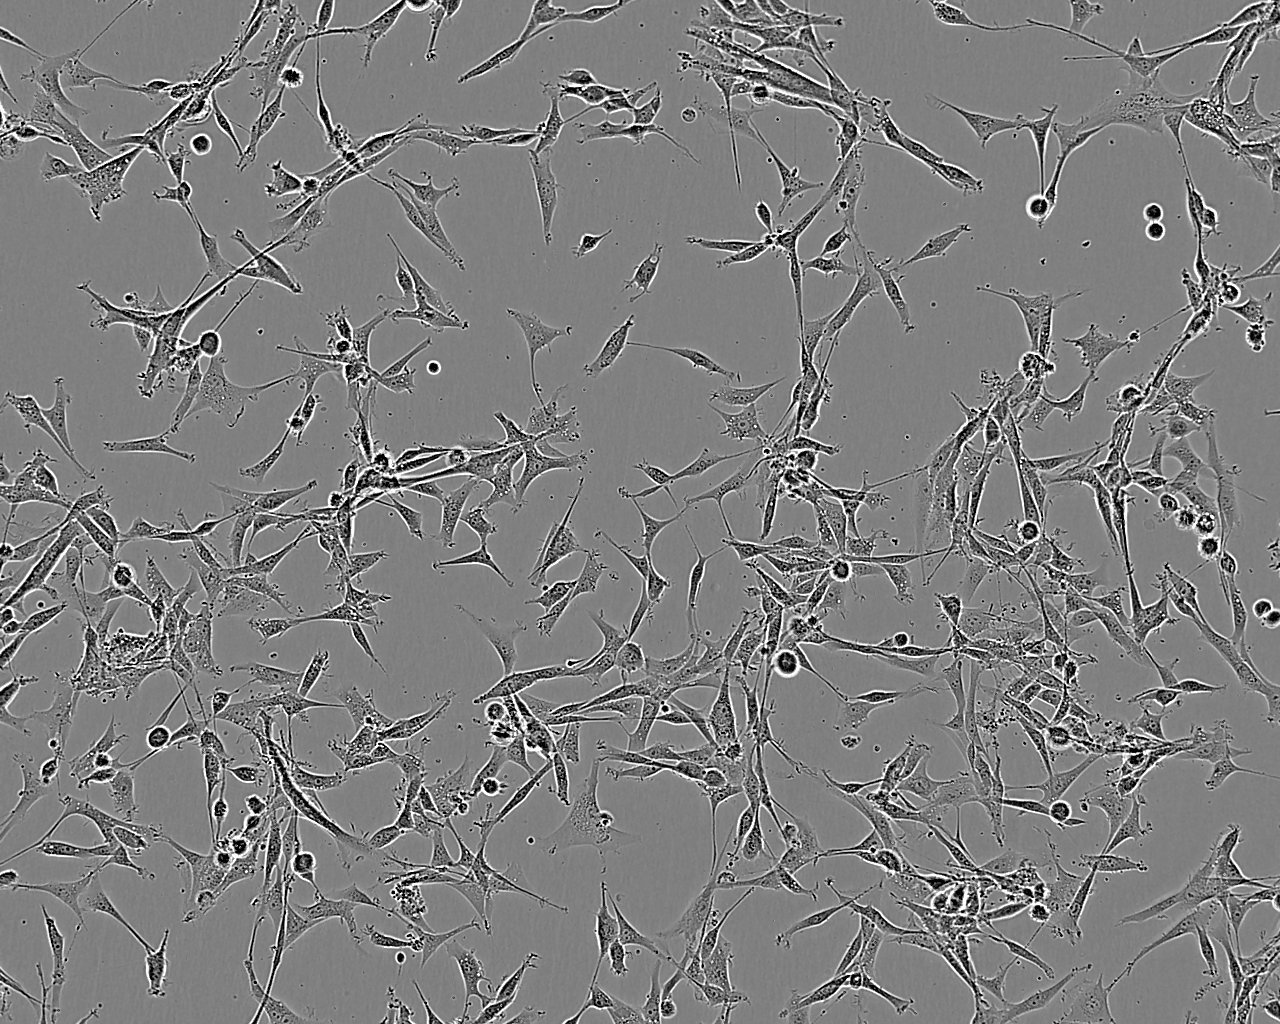

U-87 MG

Important information: Please refer to Allen M, et al. Origin of the U87MG glioma cell line: Good news and bad news. Sci. Trans. Med. 8(354): 1-4, 2016 Derived from a malignant glioma from a female patient by explant technique. It is reported to produce a malignant tumour consistent with glioblastoma in nude mice.